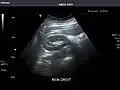

Renal ultrasonography

Ultrasound scan of a kidney (right side)

Ultrasonography of the kidneys is essential in the diagnosis and management of kidney-related diseases. The kidneys are easily examined, and most pathological changes in the kidneys are distinguishable with ultrasound.[7]